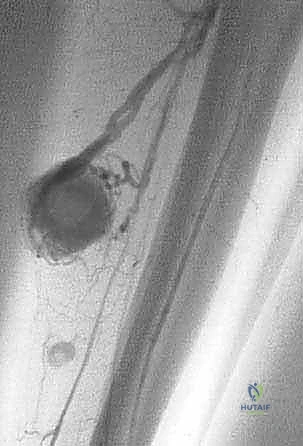

الحالة الأولى: إنقاذ ركبة رياضي شاب

شاب يبلغ من العمر 19 عاماً عانى من ألم مستمر في الركبة وتورم لم يستجب للمسكنات. بعد الفحص السريري الدقيق وإجراء الرنين المغناطيسي، اشتبه الأستاذ الدكتور محمد هطيف بوجود ورم. تم إجراء خزعة إبرة أساسية دقيقة جداً. أظهرت النتائج وجود "ساركوما عظمية" في مراحلها الأولى. بفضل الخزعة الدقيقة التي لم تلوث الأنسجة المحيطة، تمكن الدكتور هطيف لاحقاً من استئصال الورم بالكامل وتركيب مفصل صناعي خاص بالأورام، مما أنقذ ساق الشاب من البتر ومكنه من العودة للمشي بشكل طبيعي.